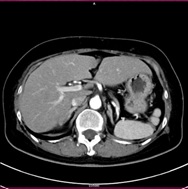

胸部CT 腹部CT

胸部CT画像               腹部CT画像